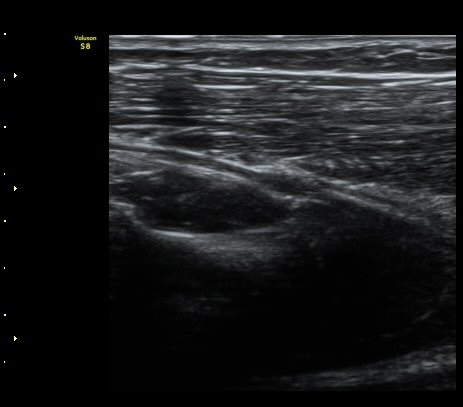

ÃÊÀ½ÆÄ °Ë»ç